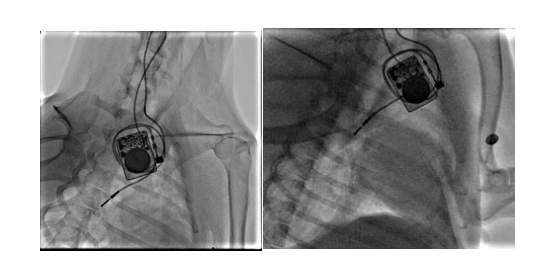

团队构建犬的慢性房颤动物模型,分析无创体表心电标测和有创心外膜心电标测系统采集的心电信号的相关性。我们通过经颈静脉介入(图10)和右外侧开胸小切口(图11)两种方法建立快速起搏右心房的犬慢性房颤模型

图9 经颈静脉介入路径构建右心房快速起博犬的慢性房颤模型